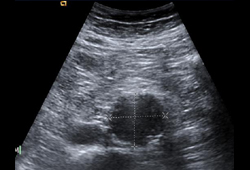

- ultrassonografia aórtica